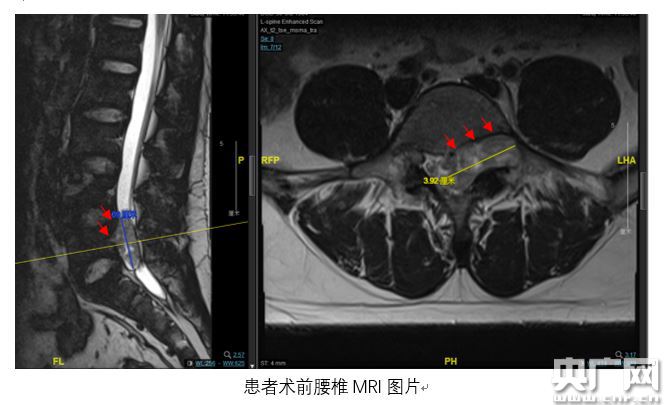

腰椎MRI檢查結(jié)果顯示,小陳腰骶部椎管內(nèi)有一個(gè)呈啞鈴型異常占位,占據(jù)了左側(cè)椎間孔且破壞到椎體骨質(zhì),憑借豐富臨床經(jīng)驗(yàn),趙杰主任診斷意見(jiàn)為椎管內(nèi)神經(jīng)鞘瘤,需盡快手術(shù)。